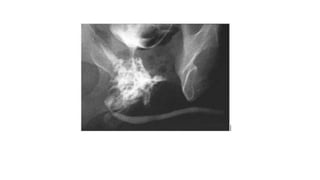

• #27 Voiding cyctourethrography in AP and oblique projections sowing bladder diverticulum